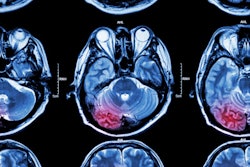

Using T1-weighted diffusion tensor MRI (DTI), Dr. Leonardo Bonilha and colleagues compared the brain scans of seven patients with dystonia with those of 10 patients without the disorder. They evaluated differences in mean diffusivity and fractional anisotropy, and found white-matter abnormalities in the patients with the dystonia.

The researchers noted that idiopathic dystonia was associated with larger fractional anisotropy values in close proximity to the insula, putamen, claustrum, precentral gyrus, and cingulate and superior frontal gyri, according to the results.

They also saw smaller fractional anisotropy values in the pallidum, parahippocampal areas, thalamus, precentral and postcentral gyri, medial and middle frontal gyri, cingulate gyrus, precuneus, cuneus, and superior temporal sulcus, said Bonhila, who is an assistant professor of neurology at the university.

Finally, "idiopathic dystonia was also associated with increase in mean diffusivity in adjacent white matter to the pallidum and putamen bilaterally, left caudate, and in subcortical hemispheric regions including the postcentral gyrus, " he added.

"Abnormal fractional anisotropy and mean diffusivity in patients with idiopathic dystonia indicate that abnormal axonal coherence and integrity contribute to the pathophysiology of dystonia," he explained.